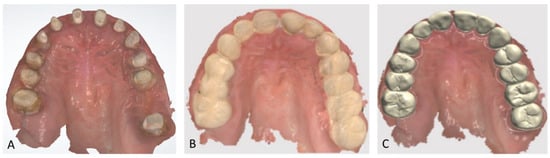

Figure 2.

Endo buccal examination: (A) maxillary arch, (B) mandibular arch, (C) dental arches in occlusion.

Extraoral examination revealed an unaesthetic smile, radiation-induced caries (Figure 1A), and mandibular retrognathia following carcinoma resection. The occlusal vertical dimension (OVD) was slightly reduced. Intraoral examination showed extensive decay in the remaining teeth (17 to 27, 36, 37, 46, and 47), with most being painful to percussion and highly sensitive to cold. Compromised restorations were noted in teeth 17, 16, 14, and 26 (Figure 2). The gingiva was inflamed and extremely sensitive, and the alveolar ridge in the mandibular incisal region was severely resorbed. Radiographic examination confirmed that 26 and 17 were non-restorable due to advanced root decay and periodontal disease (Figure 3).